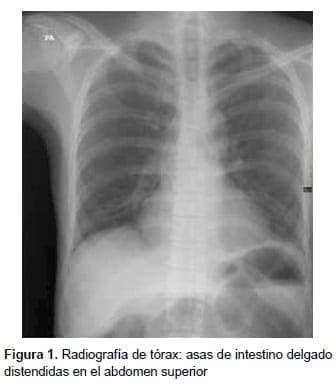

Entre sus exámenes de laboratorio se destacaba una hipopotasemia leve; en el estudio de

radiología simple de abdomen, en bipedestación y posición supina, se observó un patrón de ‘pilas de monedas’ (figuras 1-3).